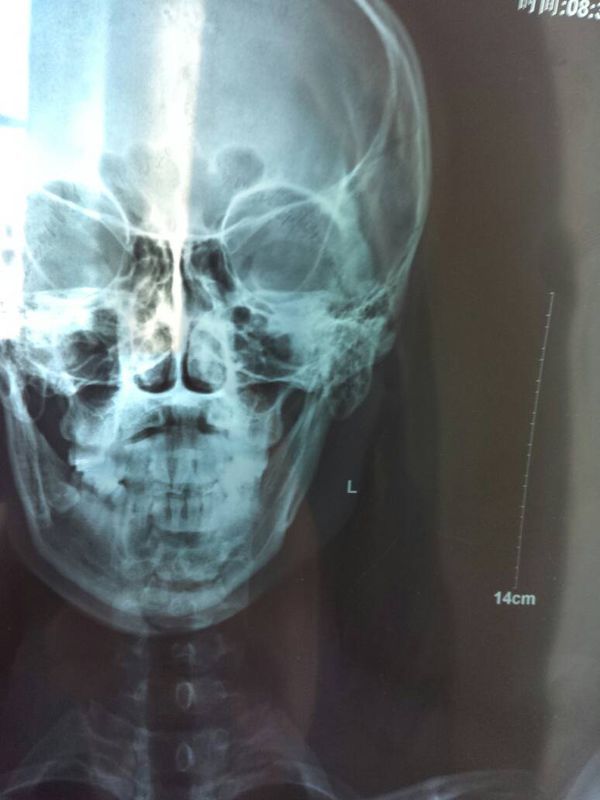

请问,这个片子L代表的是我的左脸(左手边的脸

病情分析:左脸麻木,考虑三叉问题可能性大,因为三叉神经是管理面部感觉的,而舌头左侧和左脸脸有点麻

脑血管导致的话是半身麻木,不会就是脸,2,面神经麻痹的话以口眼歪斜为主症,3,无明显外伤及侵入检查史史

全部症状:左脸比右脸大,左脸麻木,肌肉有点僵硬的感觉,请问这是什么原因,需要做磁共振吗?发病时间,